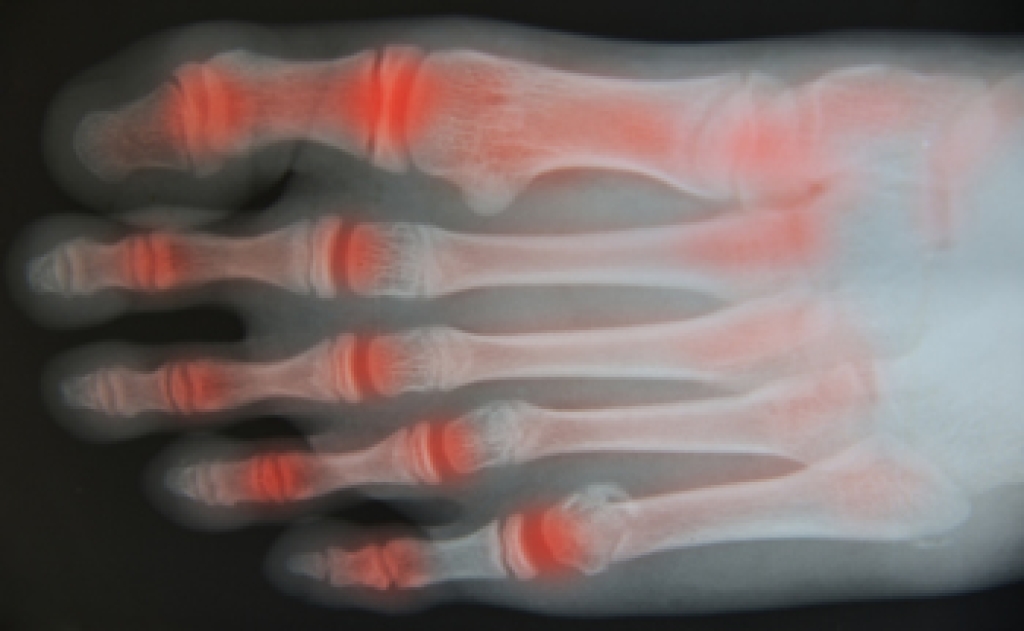

There are several joints, tendons, and muscles that are found in each foot. When arthritis in the foot develops, it can affect mobility and the range of motion may be reduced. Common symptoms of arthritic feet can consist of swelling, pain, stiffness, and in severe cases, the joints may become deformed. There are three main types of arthritis that can affect the feet. One type is osteoarthritis (OA), which is gradual wear and tear as the aging process occurs. Rheumatoid arthritis (RA) is considered to be an autoimmune disease and is often accompanied by inflammation. It may cause the foot to eventually lose function. If an injury happens to the foot, post-traumatic arthritis may occur and can affect the cartilage between the joints. Arthritis may affect balance in the feet, possibly causing the patient to become unsteady. Managing arthritic feet may be done by engaging in low-impact activity, maintaining a moderate weight, and eating healthy foods. If you have foot pain, it is strongly suggested that you speak with a podiatrist who can properly diagnose arthritis and offer the correct treatment solutions.

Arthritis is a joint disorder that involves the inflammation of different joints in your body, such as those in your feet. Arthritis is often caused by a degenerative joint disease and causes mild to severe pain in all affected areas. In addition to this, swelling and stiffness in the affected joints can also be a common symptom of arthritis.